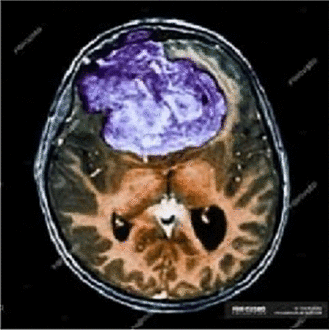

Image 1